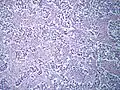

| Histopathology of classical seminoma, with typical features.[1] | |

Microscopic examination shows that seminomas are usually composed of either a sheet-like or lobular pattern of cells with a fibrous stromal network. The fibrous septa almost always contain focal lymphocyte inclusions, and granulomas are sometimes seen. The tumour cells themselves typically have abundant clear to pale pink cytoplasm containing abundant glycogen, which is demonstrable with a periodic acid-Schiff (PAS) stain. The nuclei are prominent and usually contain one or two large nucleoli, and have prominent nuclear membranes. Foci of syncytiotrophoblastic cells may be present in varied amounts. The adjacent testicular tissue commonly shows intratubular germ cell neoplasia, and may also show variable spermatocytic maturation arrest.[5]